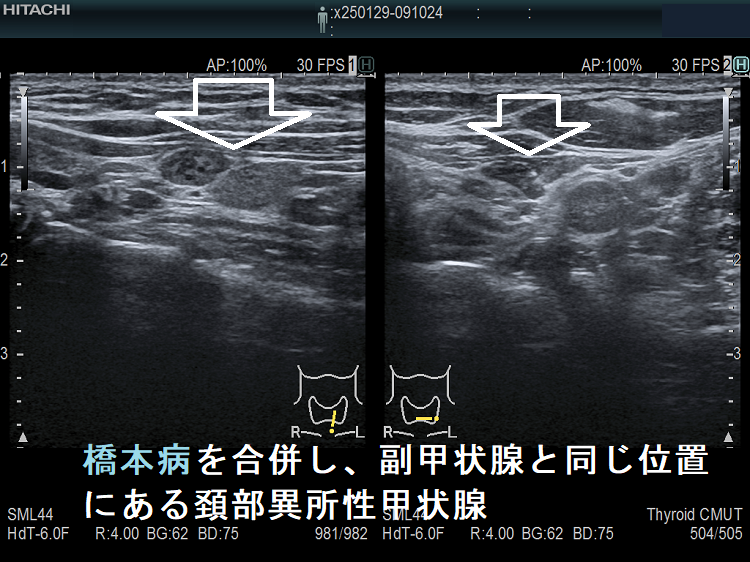

橋本病を合併し、副甲状腺と同じ位置にある頚部異所性甲状腺

ケース③

副甲状腺の位置にある頸部異所性甲状腺(非腫瘍)

頚部異所性甲状腺:下極の副甲状腺と同じ位置にある異所性甲状腺(非腫瘍)。橋本病の甲状腺本体と同様、内部粗雑な組織です。

副甲状腺の位置にある頸部異所性甲状腺(非腫瘍)ドプラーモード

副甲状腺の位置にある頸部異所性甲状腺(非腫瘍)ドプラーモード;下甲状腺動脈より下で、かつ甲状腺と連続していないため、分葉でなく異所性甲状腺。